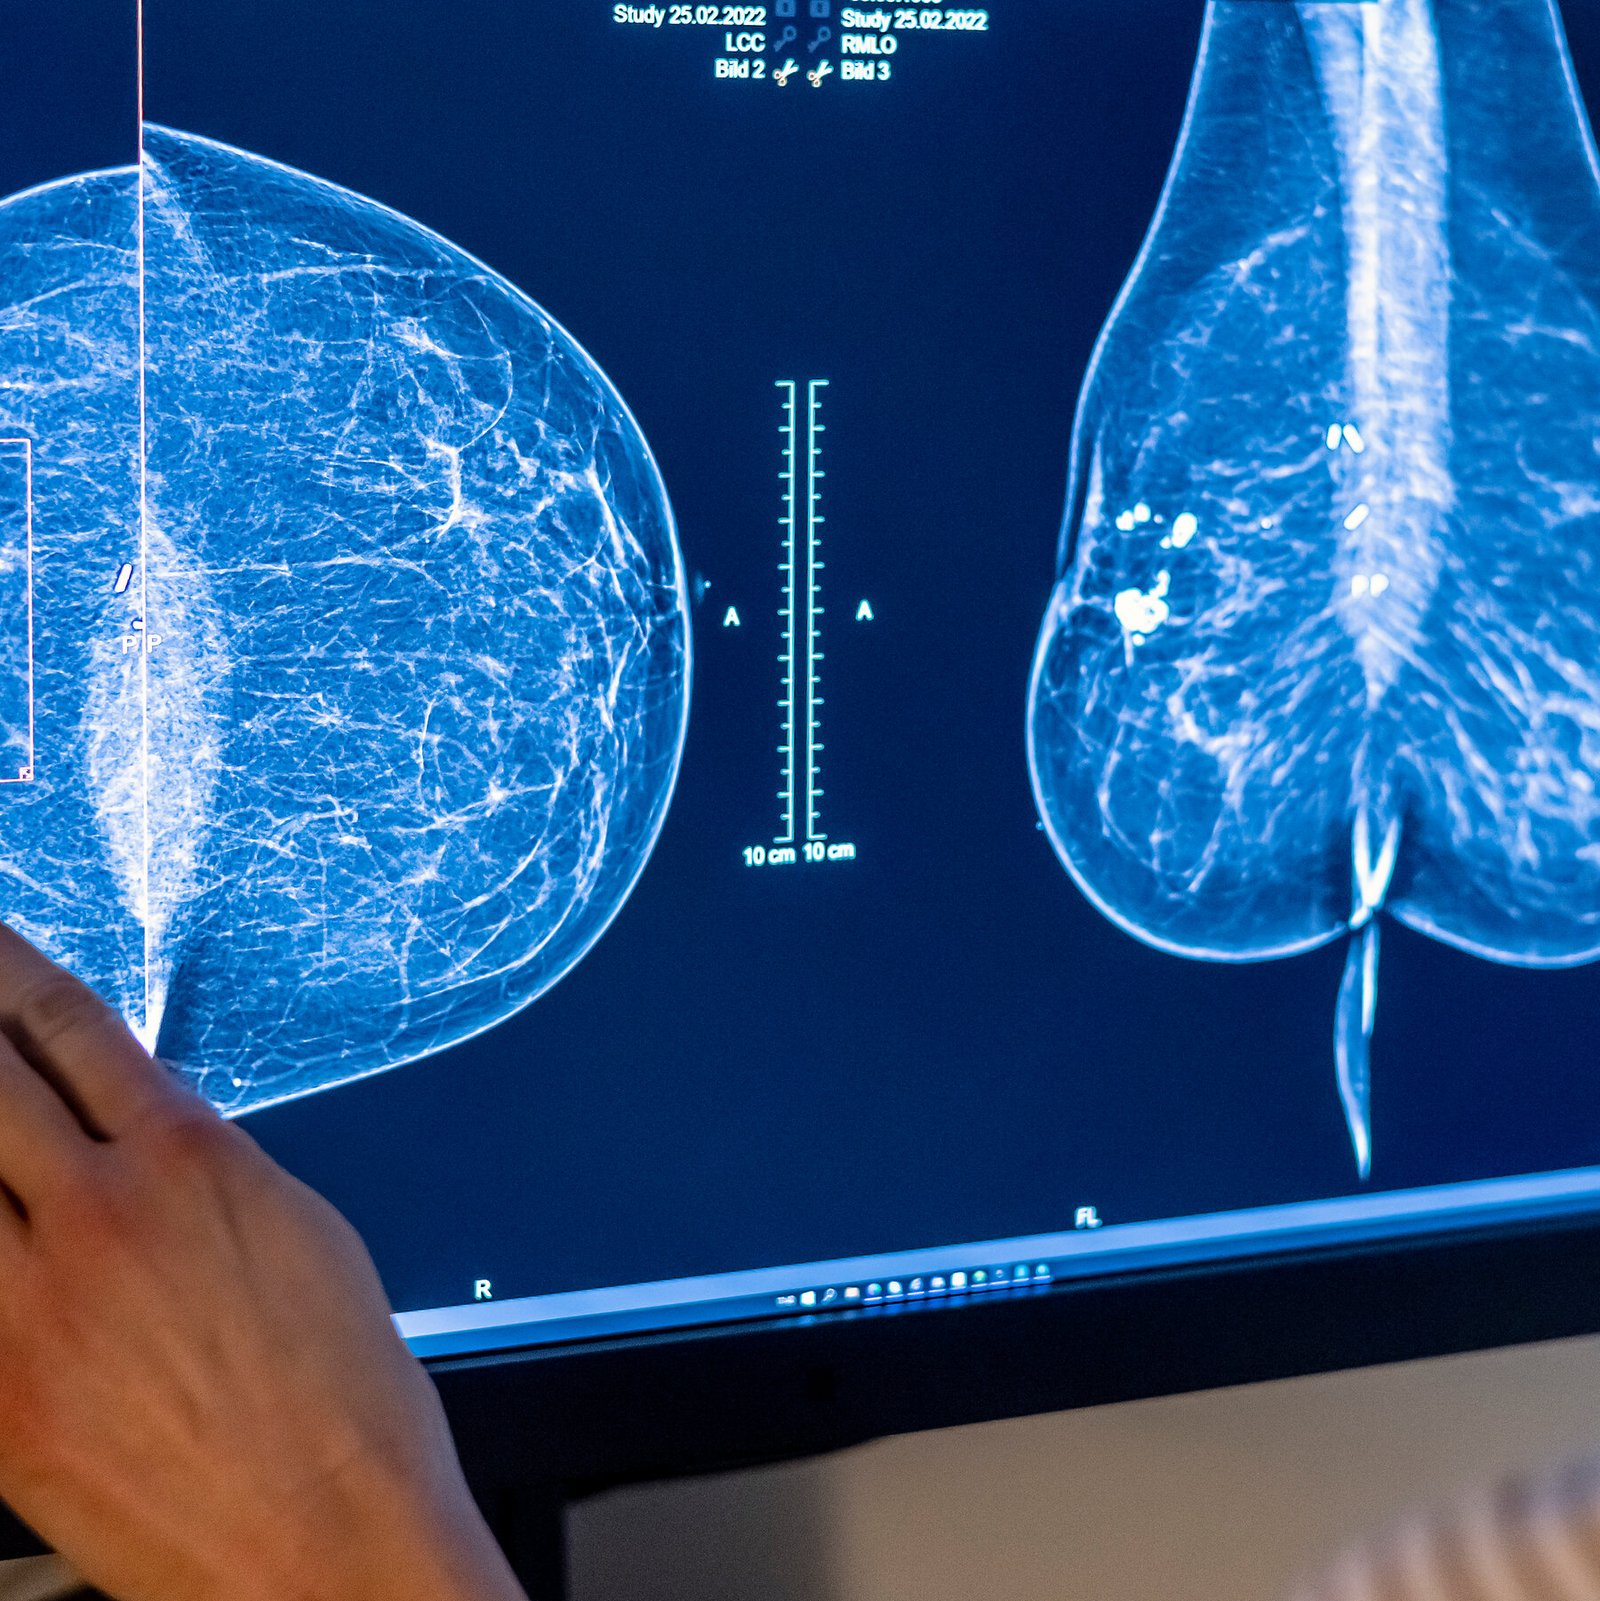

In Reversal, Expert Panel Recommends Breast Cancer Screening at 40

Some researchers said the advice did not go far enough. The panel also declined to recommend extra scans for women with dense breast tissue.